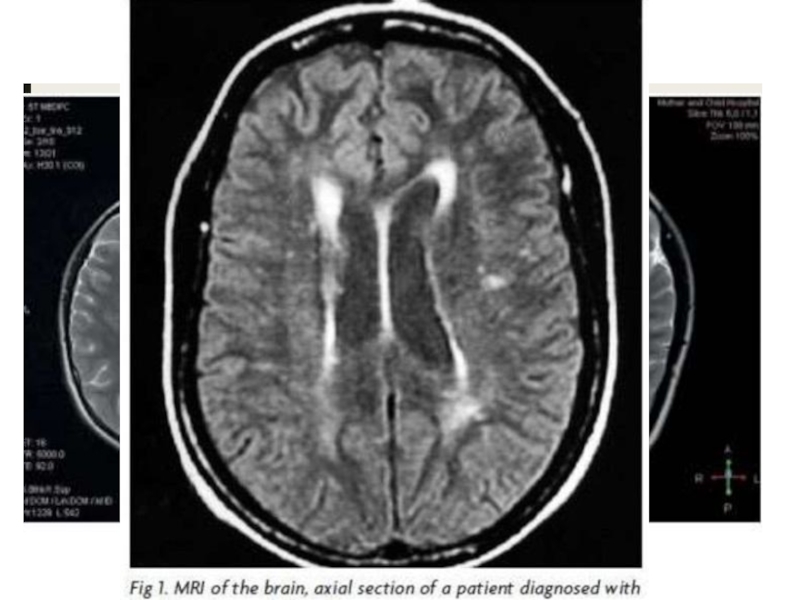

Слайд 25В единичных наблюдениях выявляли очаги повышенной интенсивности сигнала в медиальных

участках височных долей при МРТ в режиме FLAIR. У некоторых

пациентов на стадии реконвалесценции развивалась фронтотемпоральная атрофия.